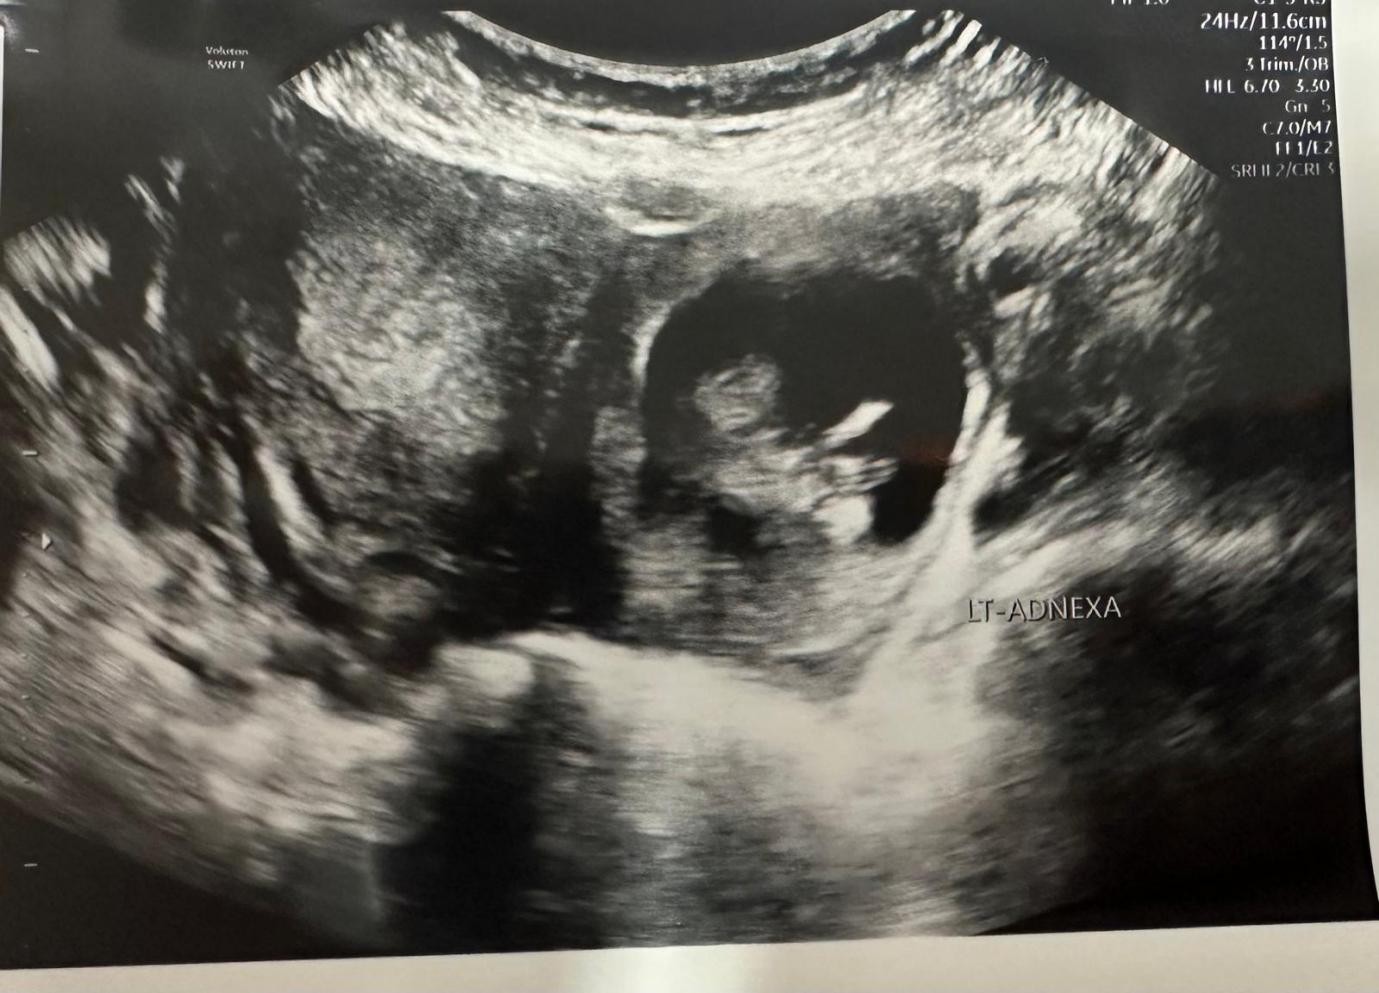

Her abdomen was mildly tender on examination with voluntary guarding. A transvaginal Ultrasound showed a viable intrauterine pregnancy at 12+4 weeks and another viable left tubal ectopic pregnancy of 11 weeks + 6 days gestation. She underwent laparoscopic surgery where a small amount of bleeding was seen in the abdomen, and an ectopic mass in the left adnexa. This mass was removed safely using Ligasure. The procedure was uncomplicated with 100mls of blood loss. She had a bedside USS post-op op which confirmed a viable intrauterinepregnancy.

Figure 1

Figure 2

Figure 3

Figure 4